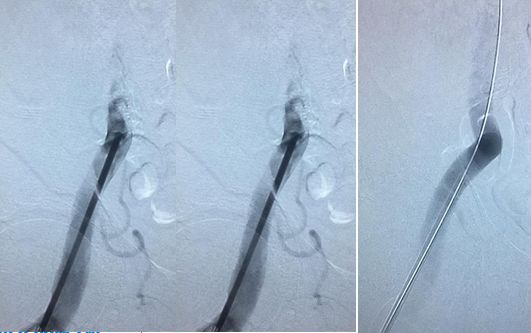

造影右侧椎动脉闭塞,右侧颈总动脉

右椎入路微导管手推造影,寻找血管闭塞位置

右椎V4段狭窄,2.5*15球囊扩张(应用替罗非班)

13:40:应用3.0*13Apollo支架释放血管再通

03-20,12时:行股动脉穿刺,血管内治疗